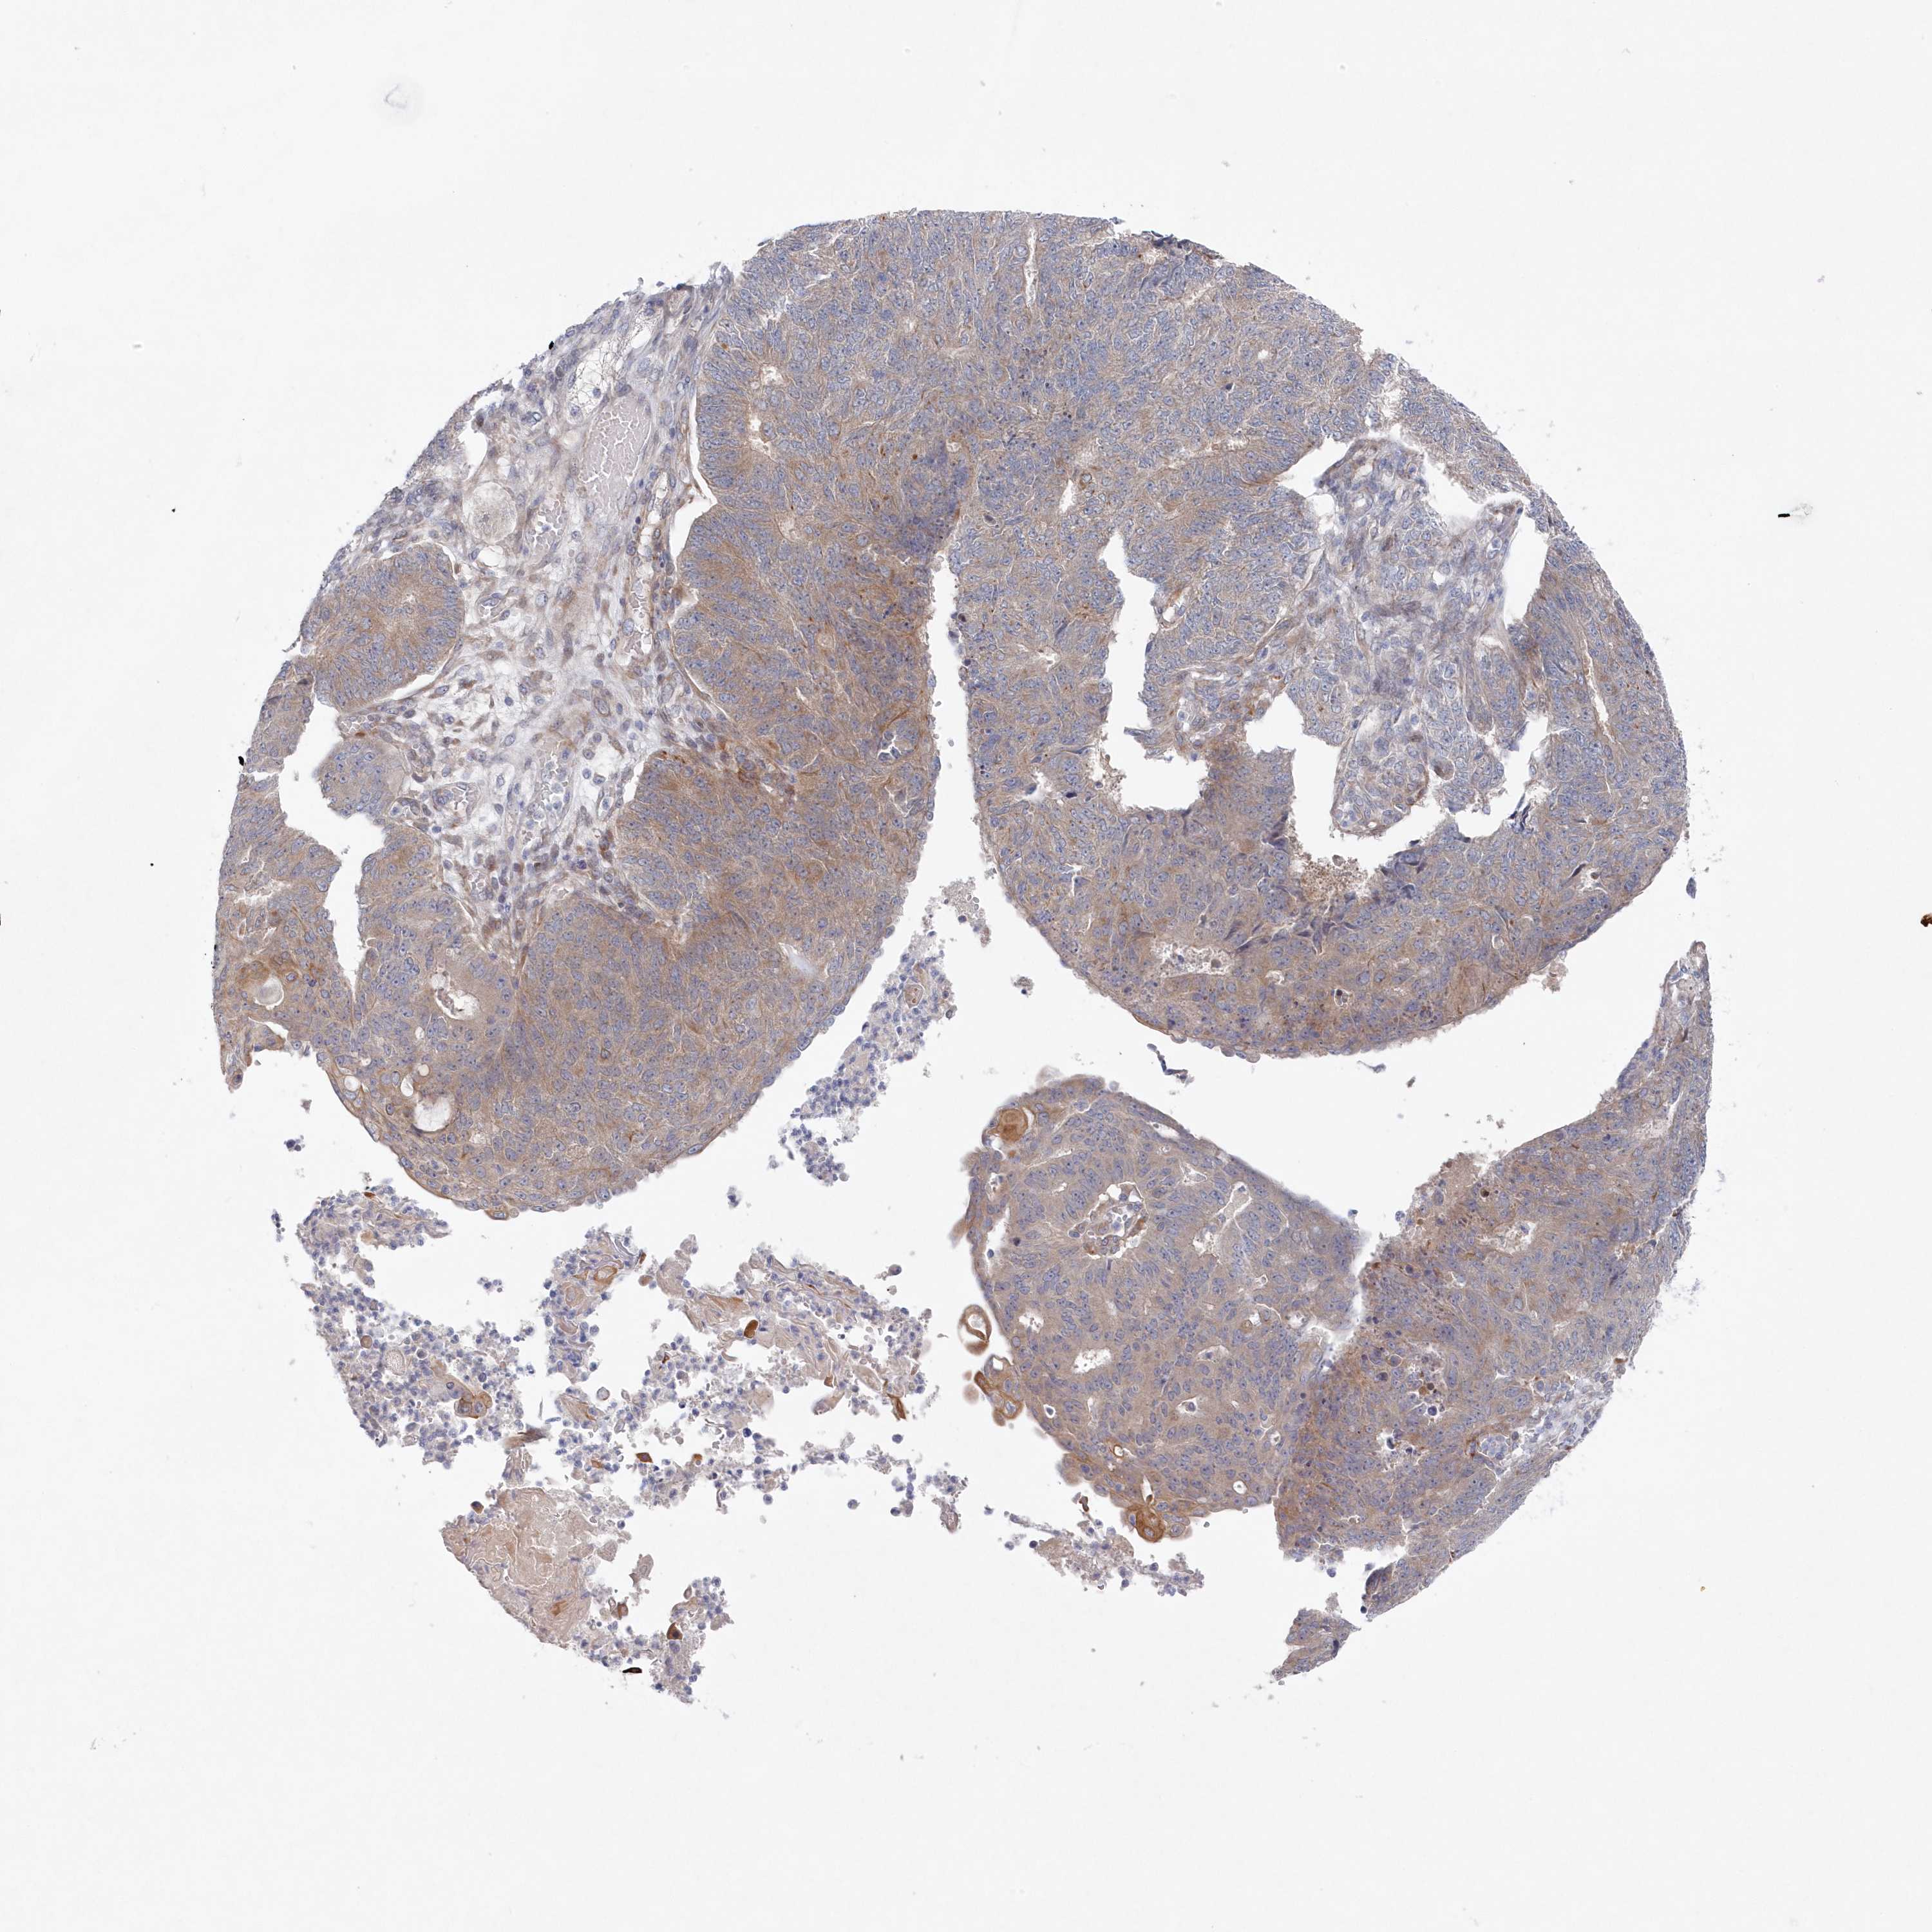

ENDOMETRIAL CANCER - Protein expressioni

A mouse-over function shows sample information and annotation data. Click on an image to view it in a full screen mode. Samples can be filtered based on level of antibody staining by selecting one or several of the following categories: high, medium, low and not detected. The assay and annotation is described here.

Note that samples used for immunohistochemistry by the Human Protein Atlas do not correspond to samples in the TCGA dataset.

Antibody stainingi

Antibody staining in the annotated cell types in the current human tissue is reported as not detected, low, medium, or high, based on conventional immunohistochemistry profiling in selected tissues. This score is based on the combination of the staining intensity and fraction of stained cells.

Each image is clickable and will lead to virtual microscopy that enables deeper exploration of all samples and also displays staining intensity scores, fraction scores and subcellular localization as well as patient and tissue information for each sample.

Antibody HPA036370

Staining

High

Medium

Low

Not detected

Intensity

Strong

Moderate

Weak

Negative

Quantity

>75%

75%-25%

<25%

None

Location

Nuclear

Cytoplasmic/membranous

Cytoplasmic/membranous,nuclear

Adenocarcinoma, NOS

Adenocarcinoma, metastatic, NOS